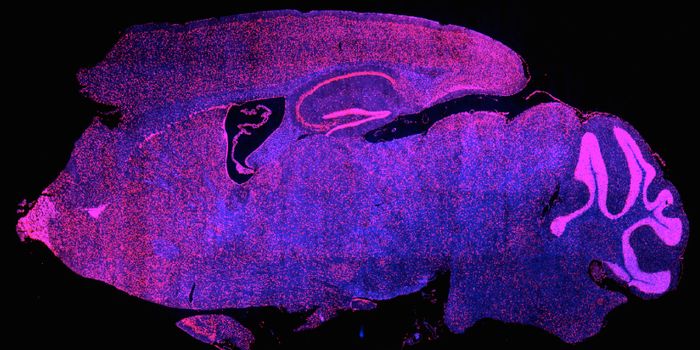

JAN 08, 2016Clinical & Molecular DXMouse models are essential to medicine and research, as they allow researchers to explore many biological processes that ...